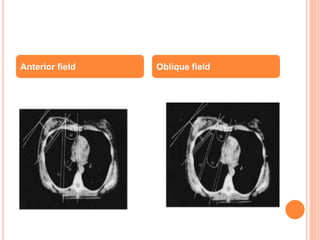

DEEP TANGENTS

 Partial Wide tangent

Anterior field Oblique field